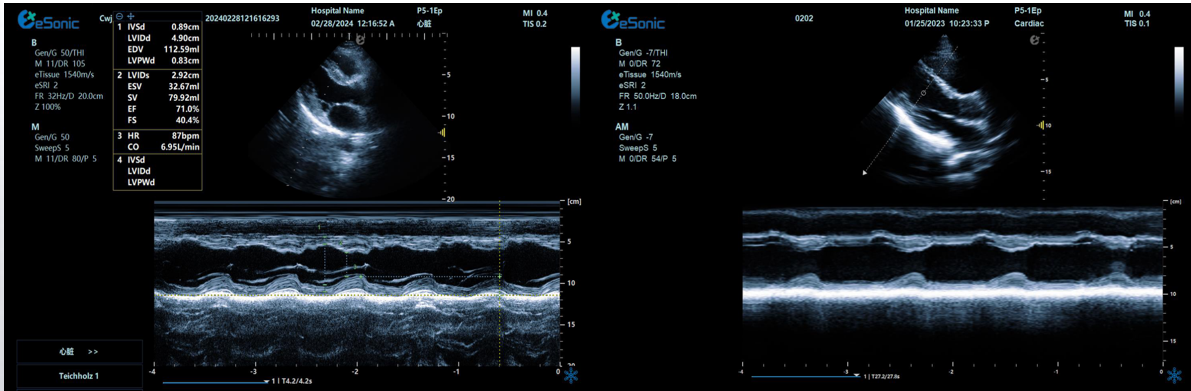

临床病例(一)

女性,68岁,临床诊断:冠心病

超声表现:左房大,左室壁运动幅度明显减低,以室间隔较明显;心包腔内见无回声区,右室前壁8mm,左室侧壁10mm。

冠心病、心包积液